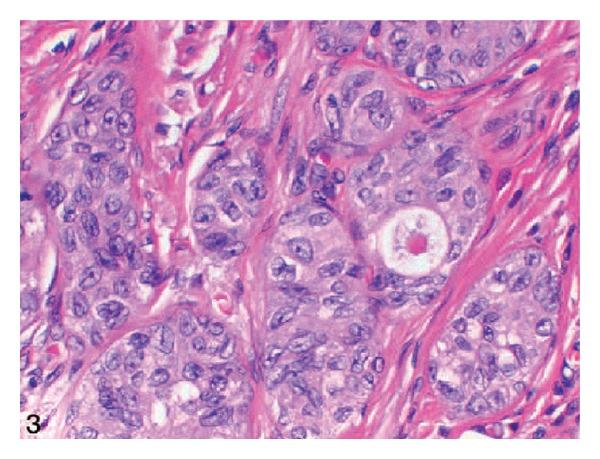

Background. Nested variant of urothelial carcinoma was added to the WHO's classification in 2004. Aims. To review the literature on nested variant of urothelial carcinoma. Results. About 200 cases of the tumour have been reported so far and it has the ensuing morphological features: large numbers of small confluent irregular nests of bland-appearing, closely packed, haphazardly arranged, and poorly defined urothelial cells infiltrating the lamina propria and the muscularis propria. The tumour has a bland histomorphologic appearance, has an aggressive biological behaviour, and has at times been misdiagnosed as a benign lesion which had led to a significant delay in the establishment of the correct diagnosis and contributing to the advanced stage of the disease. Immunohistochemically, the tumour shares some characteristic features with high-risk conventional urothelial carcinomas such as high proliferation index and loss of p27 expression. However, p53, bcl-2, or EGF-r immunoreactivity is not frequently seen. The tumour must be differentiated from a number of proliferative lesions of the urothelium. Conclusions. Correct and early diagnosis of this tumour is essential to provide early curative treatment to avoid diagnosis at an advanced stage. A multicentre trial is required to identify treatment options that would improve the outcome of this tumour.

背景。尿路上皮癌巢状变异型于2004年被纳入世界卫生组织分类。目的。回顾关于尿路上皮癌巢状变异型的文献。结果。迄今为止已报道了约200例该肿瘤病例,其具有以下形态学特征:大量小的融合性不规则巢状结构,由外观温和、紧密排列、杂乱无章且边界不清的尿路上皮细胞组成,浸润固有层和肌层。该肿瘤具有温和的组织形态学外观,具有侵袭性生物学行为,有时被误诊为良性病变,这导致正确诊断的建立出现显著延迟,并促使疾病进展至晚期。免疫组织化学方面,该肿瘤与高危传统尿路上皮癌具有一些共同特征,如高增殖指数和p27表达缺失。然而,p53、bcl-2或表皮生长因子受体免疫反应性并不常见。该肿瘤必须与多种尿路上皮增生性病变相鉴别。结论。对该肿瘤进行正确和早期诊断对于提供早期治愈性治疗以避免晚期诊断至关重要。需要进行多中心试验以确定可改善该肿瘤治疗结果的治疗方案。